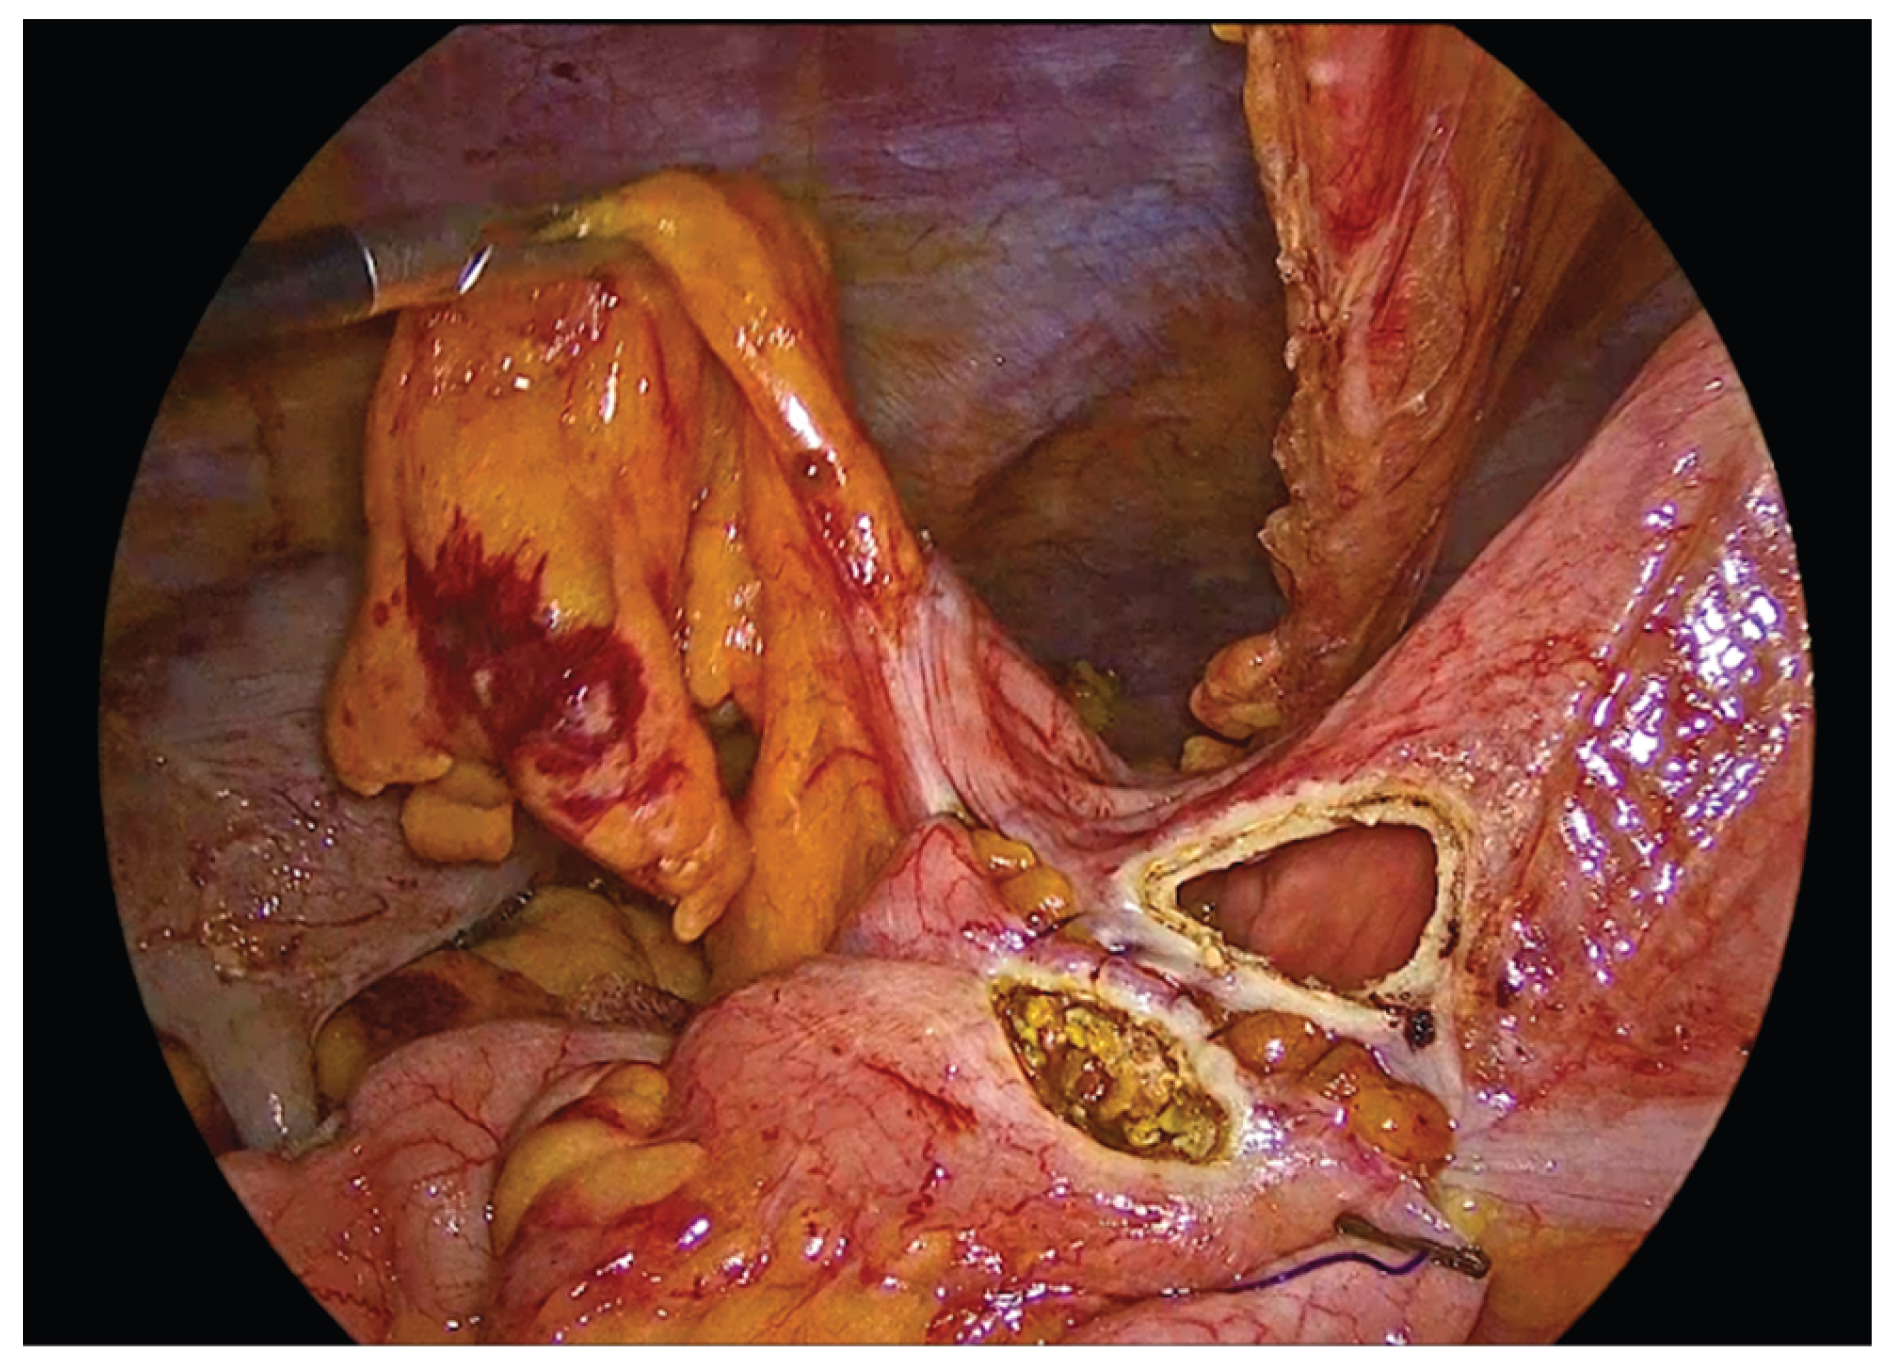

Following complete mobilization of the specimen and the transection of the mesocolon and associated vessels, the terminal ileum and transverse colon are divided using a 60mm endoscopic linear stapler. The specimen is temporarily positioned over the liver to maximize the operative field and facilitate construction of the anastomosis.

The transverse colon and terminal ileum are aligned in an isoperistaltic, side-to-side orientation, approximately 5 cm proximal to the stapled ends using barbed No.3-0 suture 15cm long. A single - layer handsewn intracorporeal anastomosis is then fashioned using a Vicryl No.3-0 suture 34cm long.

Figure 5. Alignment and positioning of the terminal ileum and transverse colon in an isoperistaltic, side-to-side configuration.

Enterotomies are subsequently created on the antimesenteric borders of both bowel segments, at approximately 1 cm from the outer suture line, with a length of 3 to 4 cm.

Figure 7. Enterotomies of bowel ends.